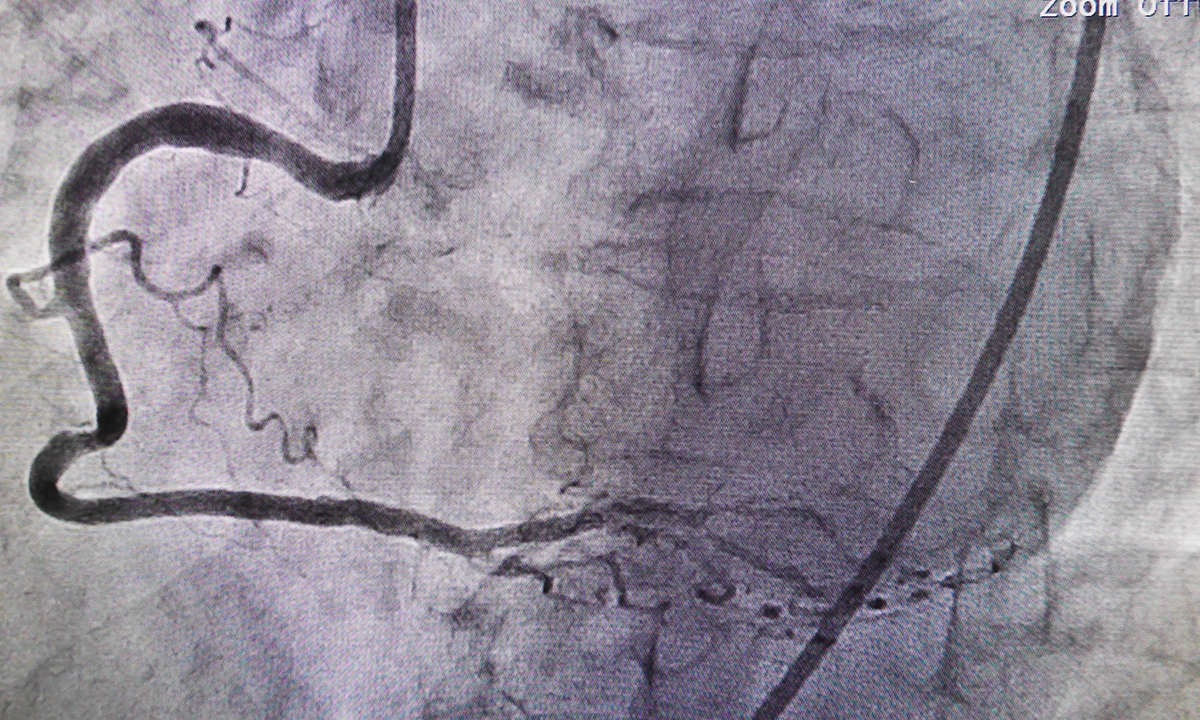

The authors wrote that CTCA, which is covered by Medicare via specialist referral, was used to evaluate chest symptoms and exclude coronary artery disease (CAD). They noted that the test has a negative predictive rate approaching 100%, so it was an “excellent ‘rule out’ test”.

Professor Hamilton-Craig said that a key benefit of CTCA was its ability to evaluate CAD non-invasively, avoiding the many risks associated with a coronary angiogram.

“The risks are significant,” he said, with an up to 1 in 1000 risk of death or major complication with angiography.

He added that an evaluation of a large United States registry had shown that around one third of patients undergoing invasive angiograms were found to be clear of CAD. “Excluding CAD can be done non-invasively using CTCA with much lower risk to the patient, so this is a much safer approach,” he said.